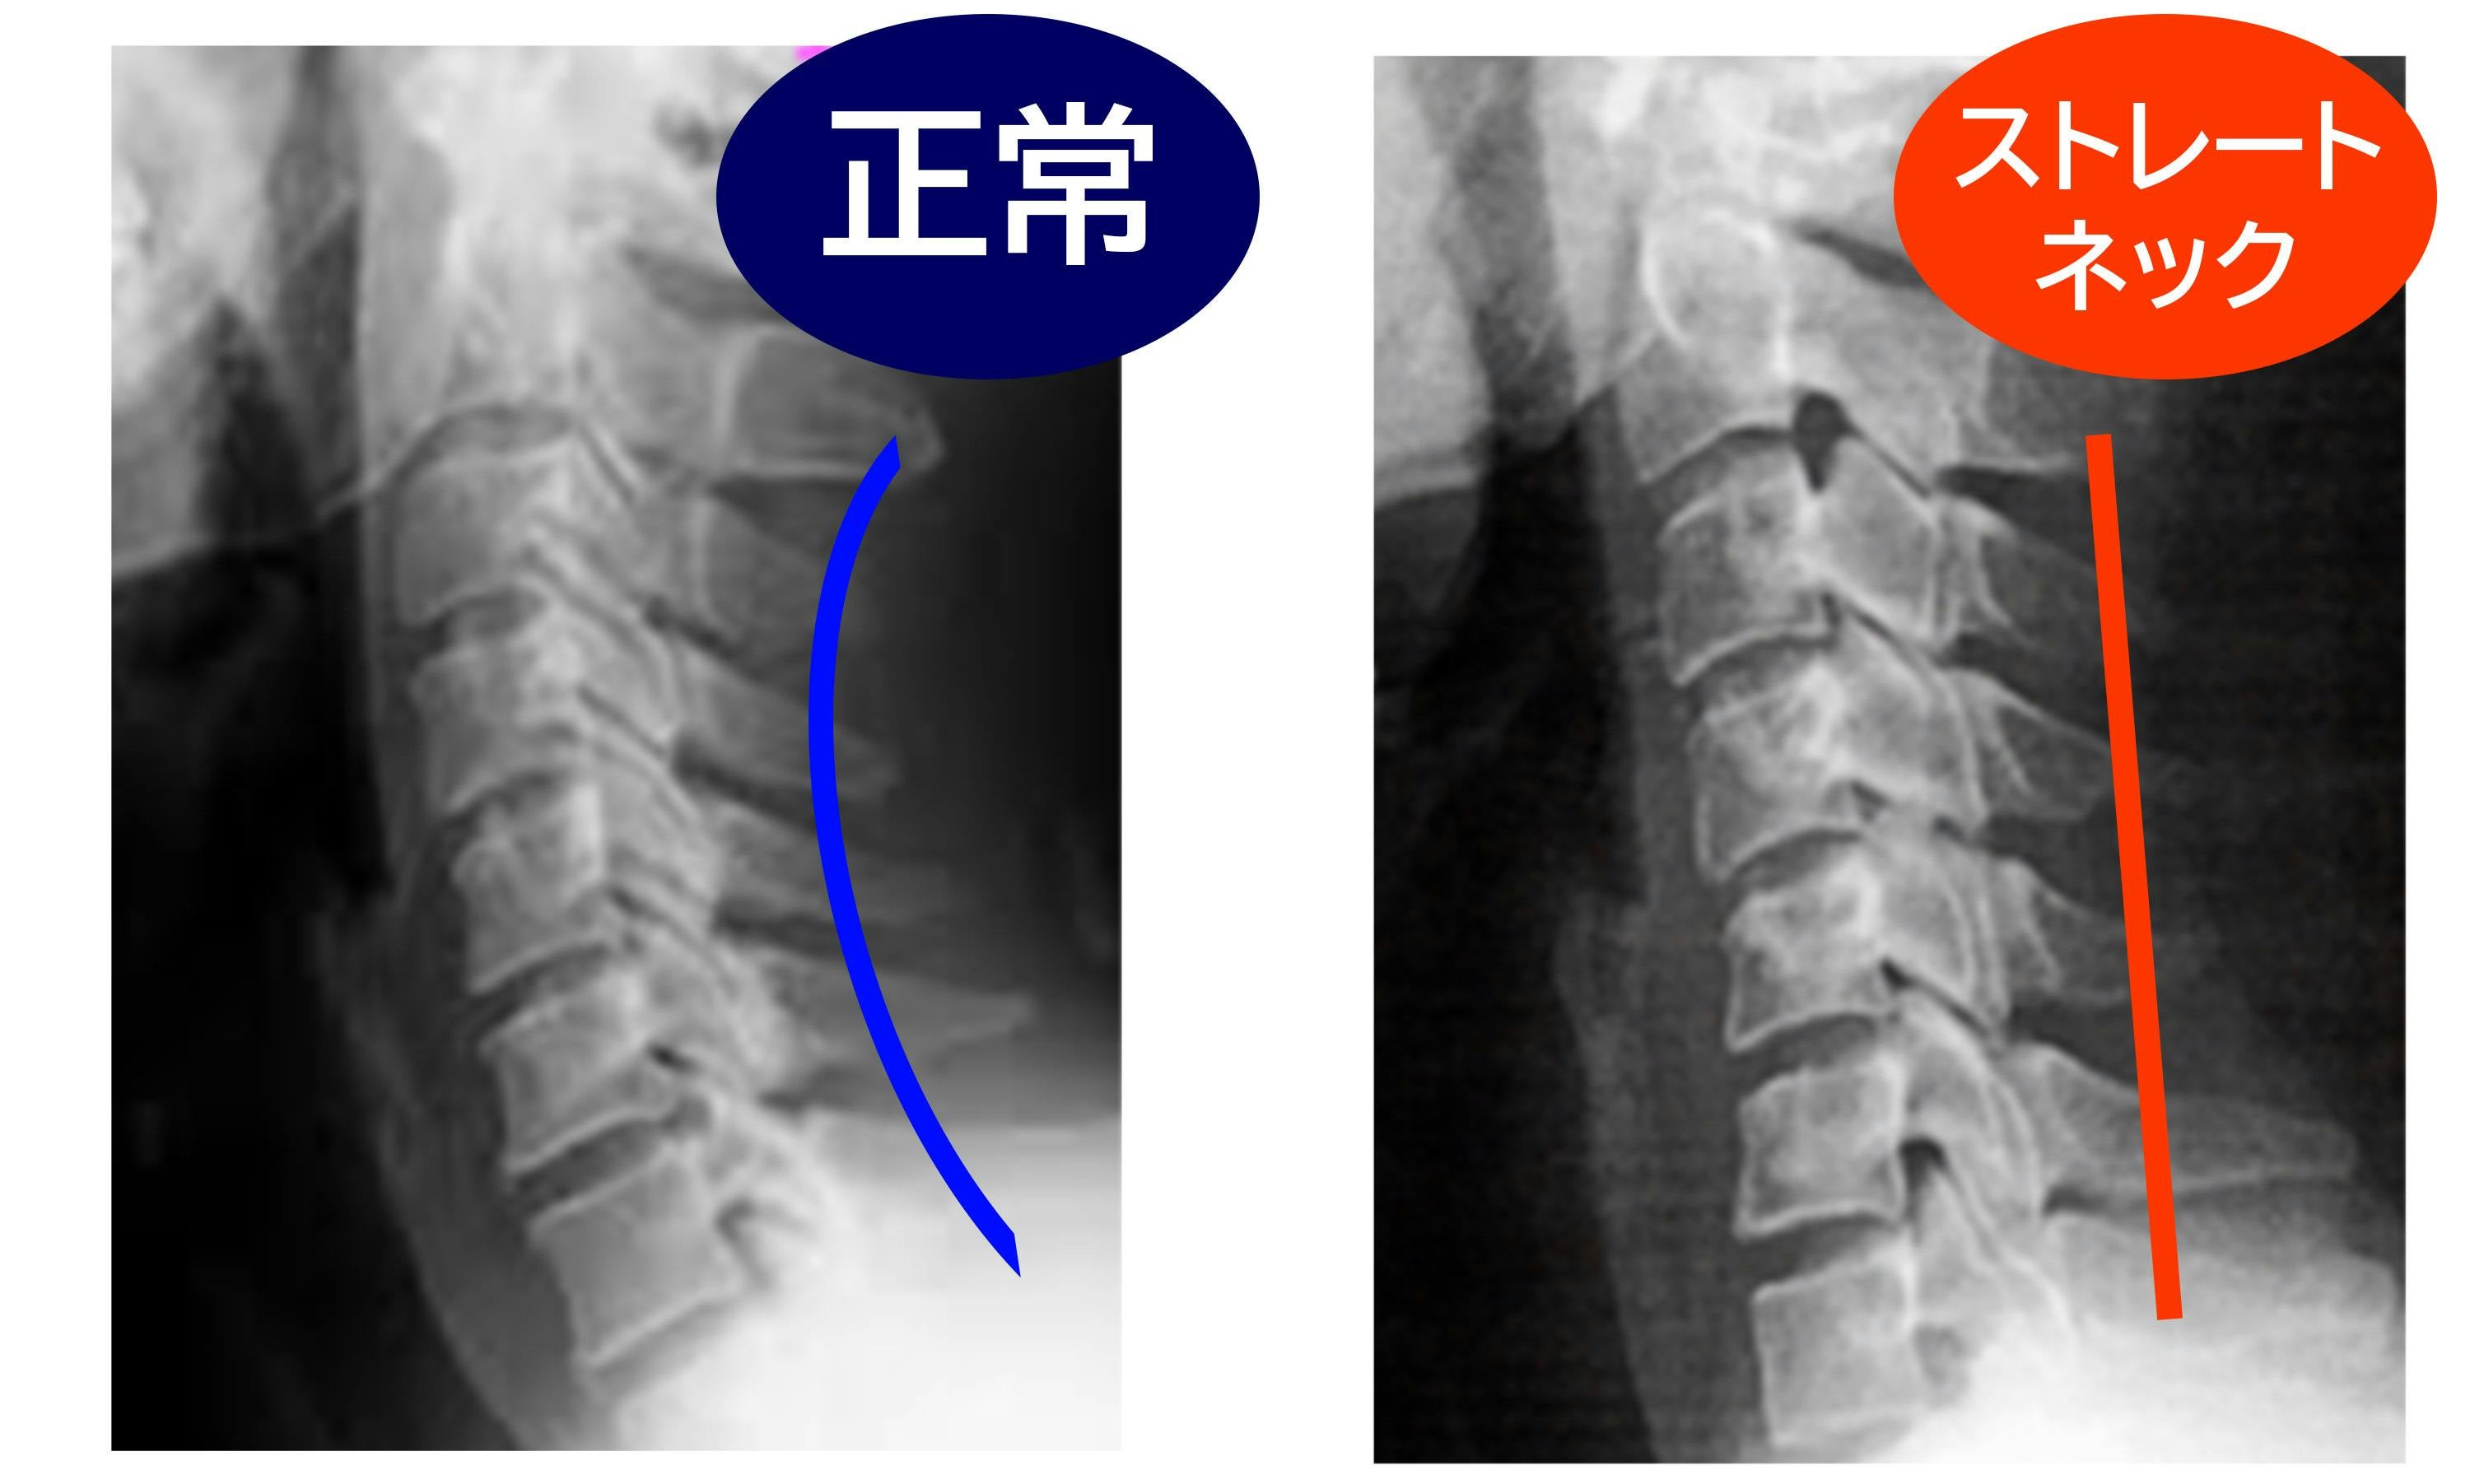

小さな画面の小さな文字や動画を追っているうちに、気づけば前かがみの姿勢をずっと続けていたということ、きっと誰でも経験があると思います。

現代に蔓延するストレートネックを何とかしたい。私は鍼灸師・柔道整復師の先生に監修に入っていただき、快眠枕「安眠二郎」の商品開発に乗り出しました。

誰でも簡単に健康な頸椎曲線を目指せる快眠枕の開発を進めました。